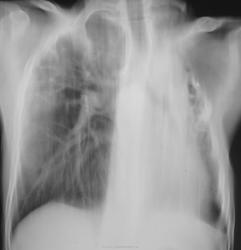

Валентин Львович, где Вы берете такие снимки? Из старых архивов ПТД? Слева состояние после торакопластики, кстати, там м.б. бронхоплевральный свищ. А у меня вопрос к Вам. Без архива, как бы Вы охарактеризовали  состояние правого л-го. Старые дела или имеется свежая инфильтрация? Вопрос снимается. По моему справа имеются мелкие полости.

Пока писал ответ, появилась динамика. Чудеса.

Нет, это не архивы. Это повседневная работа. Пациент был прооперирован в начале 2011 года в ОПТД, отпущен под наблюдение фтизиатра по "месту жительства". Вторая серия (последние 4 снимка) сделаны в пятницу. Коллега фтизиатр, увидев контрольные снимки, вспомнил пациента "не хорошим словом". Больной весьма не дисциплинированный...